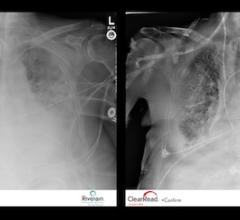

The need to improve the efficiency and quality of X-ray examinations will drive healthcare facilities across Europe to install computed radiography (CR) and digital radiography (DR) systems. The emergence of retrofit systems based on flat panel technology has popularized DR systems, and will sustain investments in the European computed and digital radiography market.